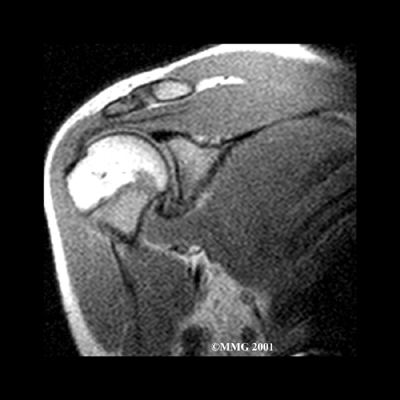

Dependendo do movimento que é capaz de executar, o seu médico poderá solicitar-lhe a realização de outros exames para afastar outras condições como a rotura dos tendões da coifa. Provavelmente, o mais comum é a Ressonância Nuclear Magnética (RNM). Uma ressonância magnética é um exame que utiliza ondas magnéticas para criar imagens em fatias com muito boa definição para os tecidos moles do ombro.

A ressonância magnética demonstra tendões e outros tecidos moles, assim como os ossos.

Ressonância Magnética colorida para ilustrar os tecidos moles.